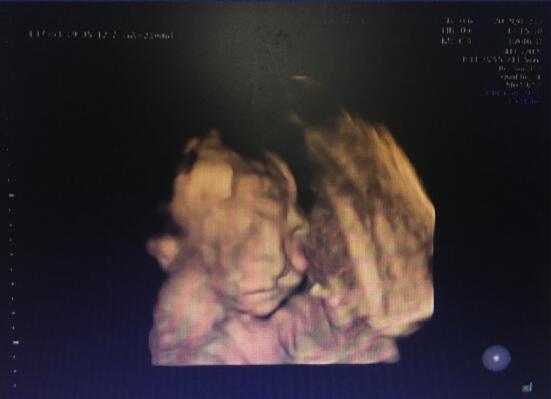

“胎兒嘴唇上有裂縫,為唇裂。”武漢仁愛醫(yī)院超聲影像科王娟主任說道。

武漢仁愛醫(yī)院超聲影像科王娟主任正在為孕婦做檢查